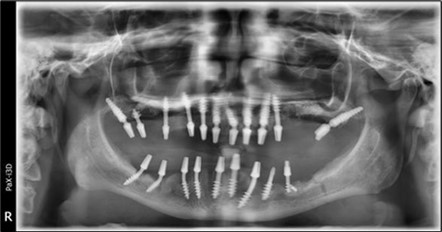

Figure 3.Panoramic pictures after removal of implants affected by peri-implantitis, extractions, alveolar crest regularization, and insertion of corticobasal and TPG implants (07.2022)